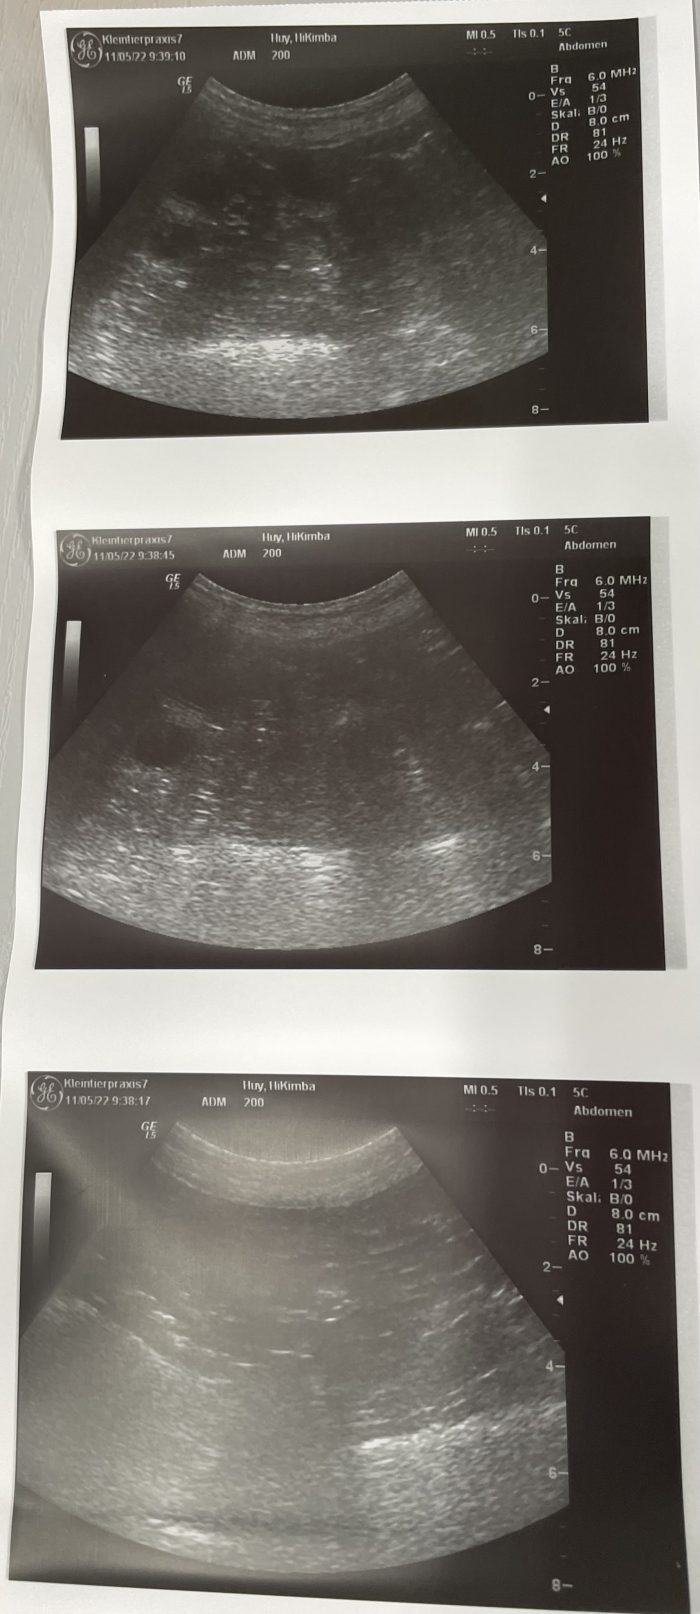

Hikimba ist trächtig ❤️

Hiki und Onyx haben sich getraut ❤️

Heute ist schon der 35 Tag, die Spannung steigt❤️